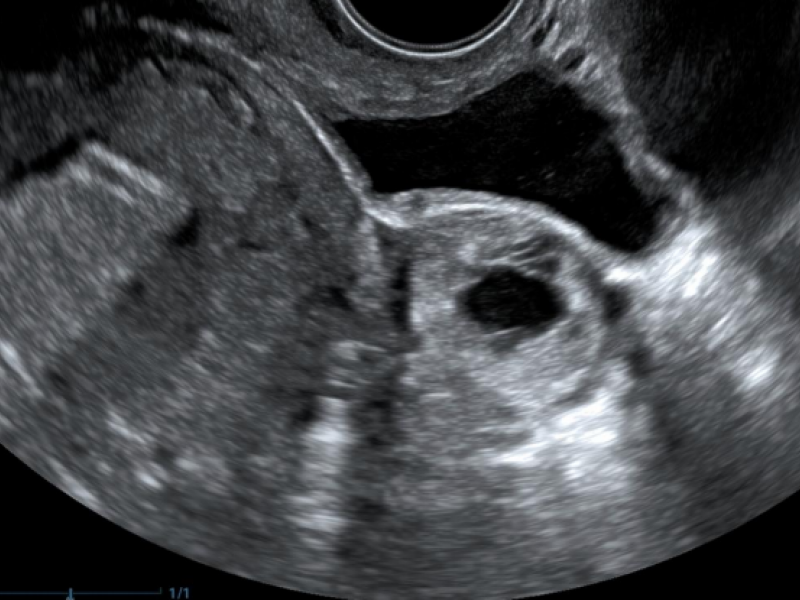

A 27 yo F presents to the ED with severe RLQ abdominal pain